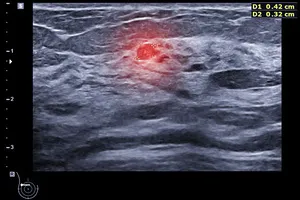

유방 초음파 검사는 고주파 음파를 이용해 유방 내부를 영상화하며, 방사선 노출 위험이 없어 임산부나 젊은 여성도 안심하고 받을 수 있습니다. 유방촬영술에서 이상 소견이 발견되거나 멍울이 만져질 때 추가적인 정밀 진단으로 사용됩니다.

- 낭종 (물혹): 액체로 채워진 주머니 형태의 혹, 초음파에서 명확하게 확인됩니다.

- 불규칙한 모양, 경계가 불분명함, 주변 조직 침윤 등의 특징, 조직 검사를 통해 최종적으로 확진됩니다.